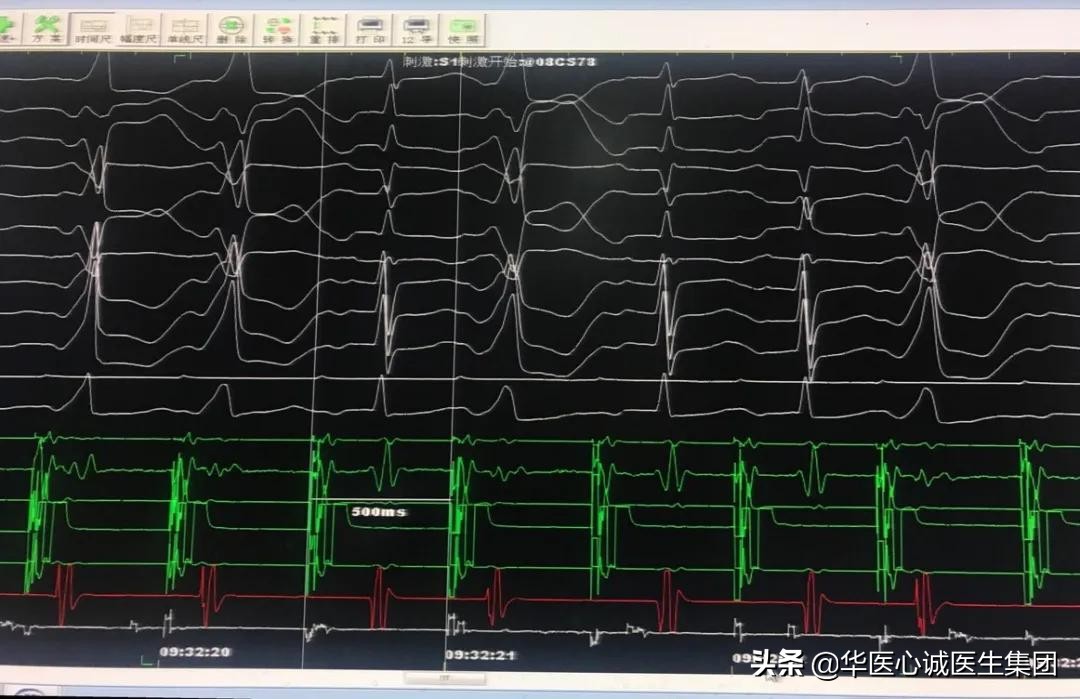

自上而下依次为:

- CS78刺激 500ms,可见旁道间歇性前传

- RV刺激 500ms,可见旁道逆传

- 术中标测过程中发生房颤